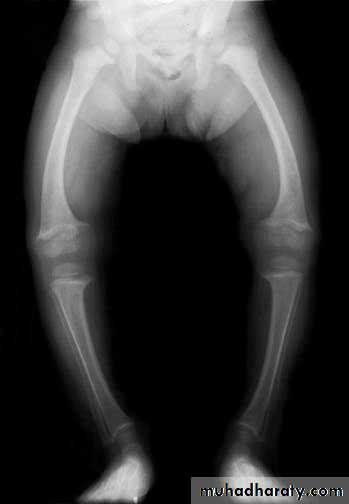

Plain radiography. Anterior-posterior view of bilateral knees. Note the irregular areas of lacy and serpentine calcific deposits in bilateral distal femurs and proximal tibias typical for bone infarcts.

AVN occurs primarily in medullary space of long bones, hands, growing

epiphyses

* Bone sclerosis from infarctions

* Dactylitis (hand-foot syndrome): bone infarcts of hands and feet